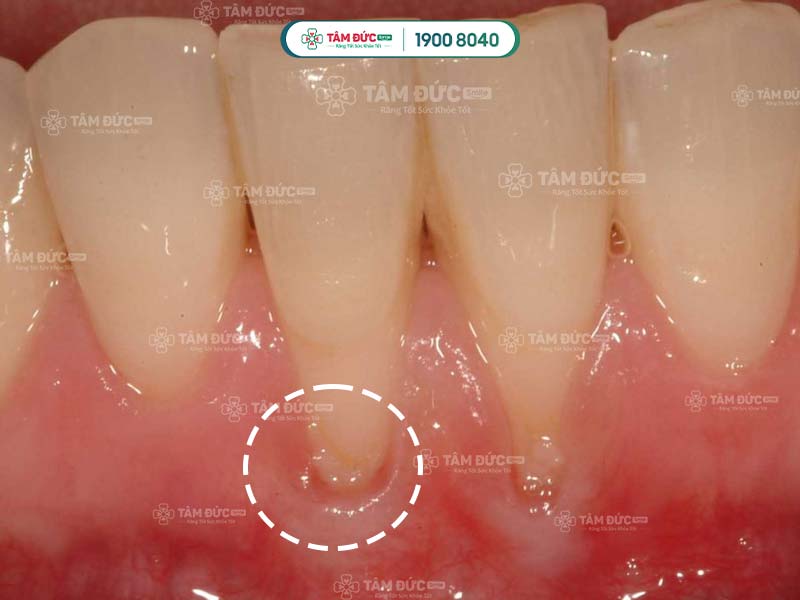

Các bác sĩ đã khẳng định rằng, tụt lợi là bệnh lý không thể tự khỏi, vì lợi là mô mềm không có khả năng tự phục hồi.

Hiện tượng tụt lợi khá phổ biến, có thể xuất hiện ở cả trẻ em và người lớn. Nếu chỉ quan sát bằng mắt thường, Quý khách sẽ rất khó để phát hiện ra tình trạng này. Đến khi xuất hiện biểu hiện rõ rệt, tụt lợi đã tiến triển sang giai đoạn nghiêm trọng. Lợi bị tổn thương không thể tự chữa lành mà cần được điều trị chuyên sâu tại nha khoa.

Nếu tụt lợi ở mức độ nhẹ, Quý khách hãy điều chỉnh chế độ ăn uống và làm sạch răng miệng để giúp lợi mau hồi phục. Ngược lại, nếu tụt lợi nghiêm trọng, Quý khách cần nhanh chóng đến nha khoa thăm khám và chữa trị chuyên sâu.

Nếu Quý khách bị tụt lợi ở mức độ nghiêm trọng sẽ không thể tự khắc phục tại nhà mà cần đến nha khoa để điều trị. Sau khi thăm khám, bác sĩ sẽ kê đơn thuốc cho Quý khách và tư vấn phương pháp điều trị thích hợp. Đến với nha khoa uy tín, Quý khách có thể ngăn chặn được các biến chứng nguy hiểm do tụt lợi gây ra.

Căn cứ vào mức độ bị tụt lợi và tổn thương, bác sĩ có thể chỉ định điều trị bằng 1 trong 3 phương pháp sau: Lấy cao răng, ghép lợi bằng phẫu thuật hoặc ghép xương răng.